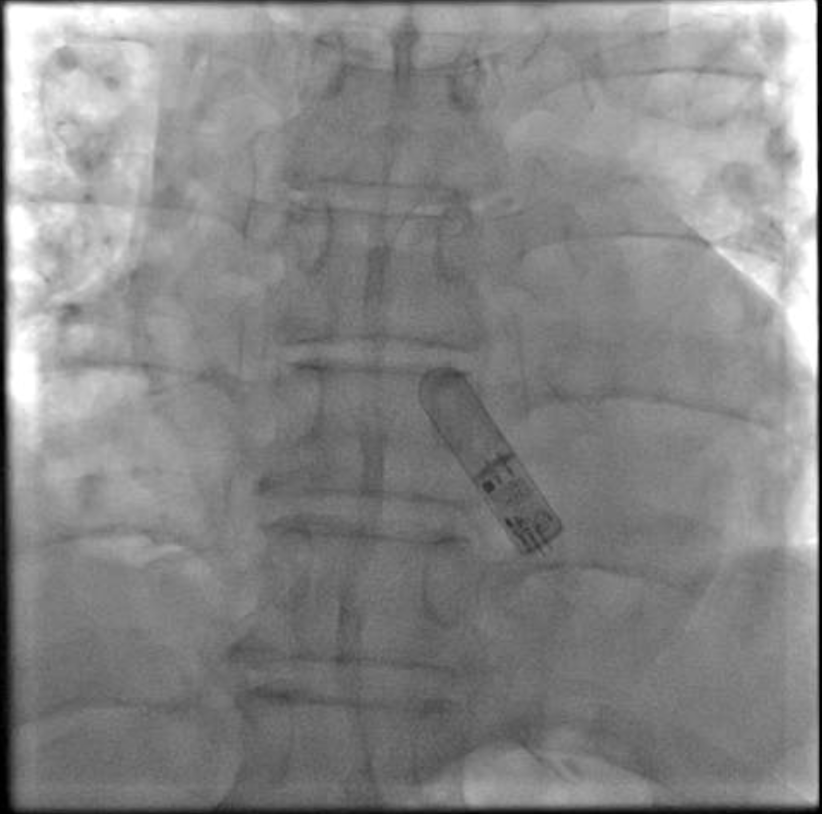

Assert-IQ ICM植入术后影像

ICM植入是一项非常简单快捷的手术,在局部麻醉条件下即可完成。常规消毒铺巾后,医生在ICM植入工具的引导下,将其推入患者第4肋间距胸骨2cm处的皮下预定位置,后缝合包扎,整个过程时间短、创伤小、出血少。术后,患者生命体征平稳,已在术间完成首次设备程控与远程连接测试,机器识别和监测心率信号非常清晰准确。今后,一旦患者再次出现晕厥、心悸或可疑症状,该设备将自动记录发作前后的心电图,并连同发作时体位、活动水平等信息保存其中,让过去不明原因的发作,变成可以反复回看的客观证据。